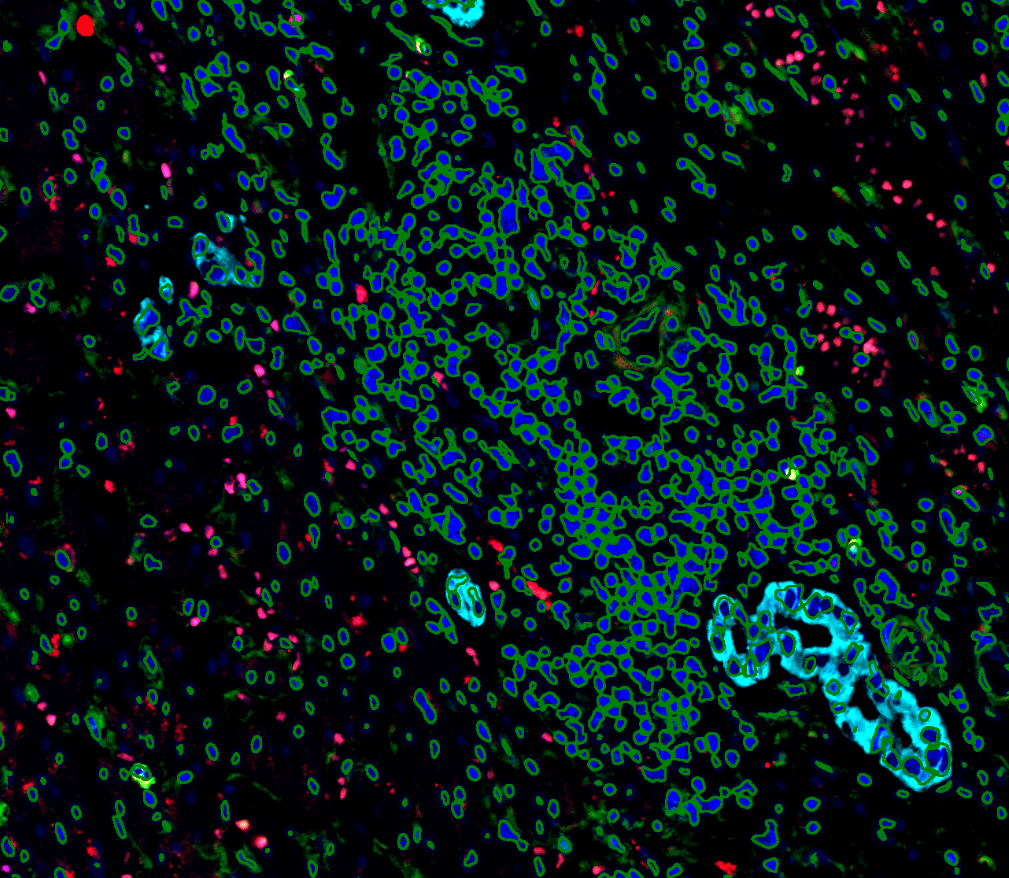

深度神經網路(DNN)核分割算法,即使在高密度細胞環境中也能精確識別

細胞鄰近性測量(Cellular Neighborhood)、空間關係分析,揭示組織微環境複雜交互作用

- 核分割算法:深度神經網路技術,準確分割各種形狀和大小的細胞核

- 空間關係分析:量化細胞間距離、密度和分佈模式

- 表型交互作用:分析不同細胞亞群之間的空間關聯性